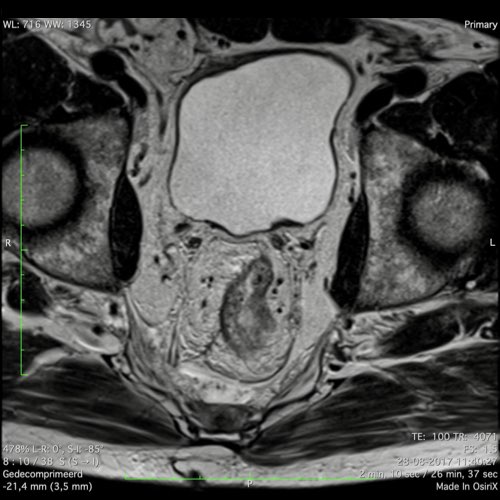

Hình ảnh

Các hình ảnh được cung cấp cho thấy ung thư biểu mô tế bào nhẫn với tình trạng dày lan tỏa thành trực tràng, hình ảnh bia bắn điển hình, và sự xâm lấn mỡ mạc treo trực tràng.